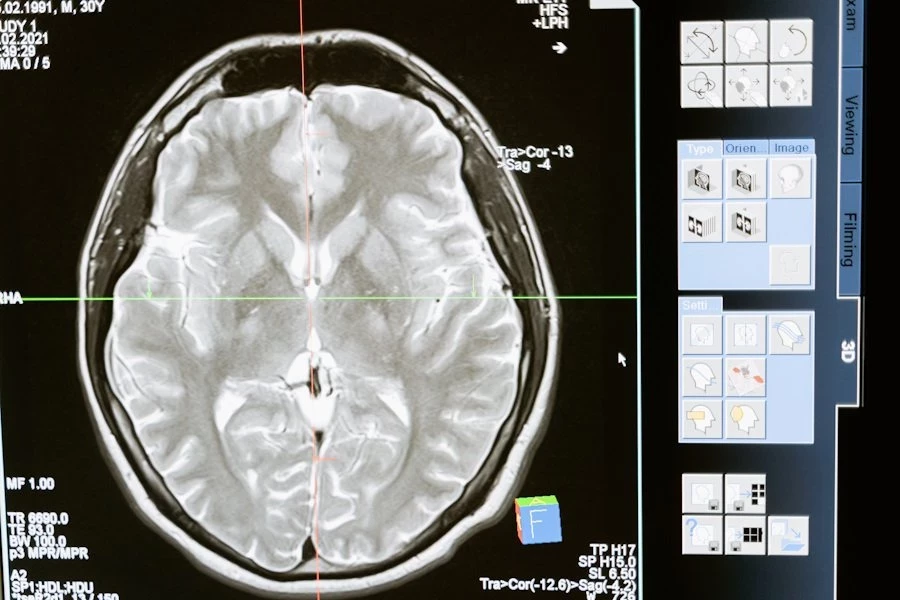

Фото из открытых источников